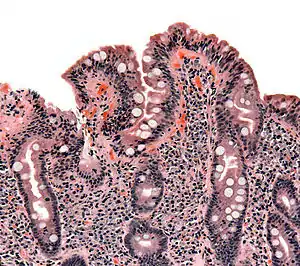

| The ileocecal valve prevents reflux of bacteria from the colon into the small bowel. Resection of the valve can lead to bacterial overgrowth. | |

Finally, abnormal connections between the bacteria-rich colon and the small bowel can increase the bacterial load in the small bowel. Patients with Crohn's disease or other diseases of the ileum may require surgery that removes the ileocecal valve connecting the small and large bowel; this leads to an increased reflux of bacteria into the small bowel. After bariatric surgery for obesity, connections between the stomach and the ileum can be formed, which may increase bacterial load in the small bowel.[27]